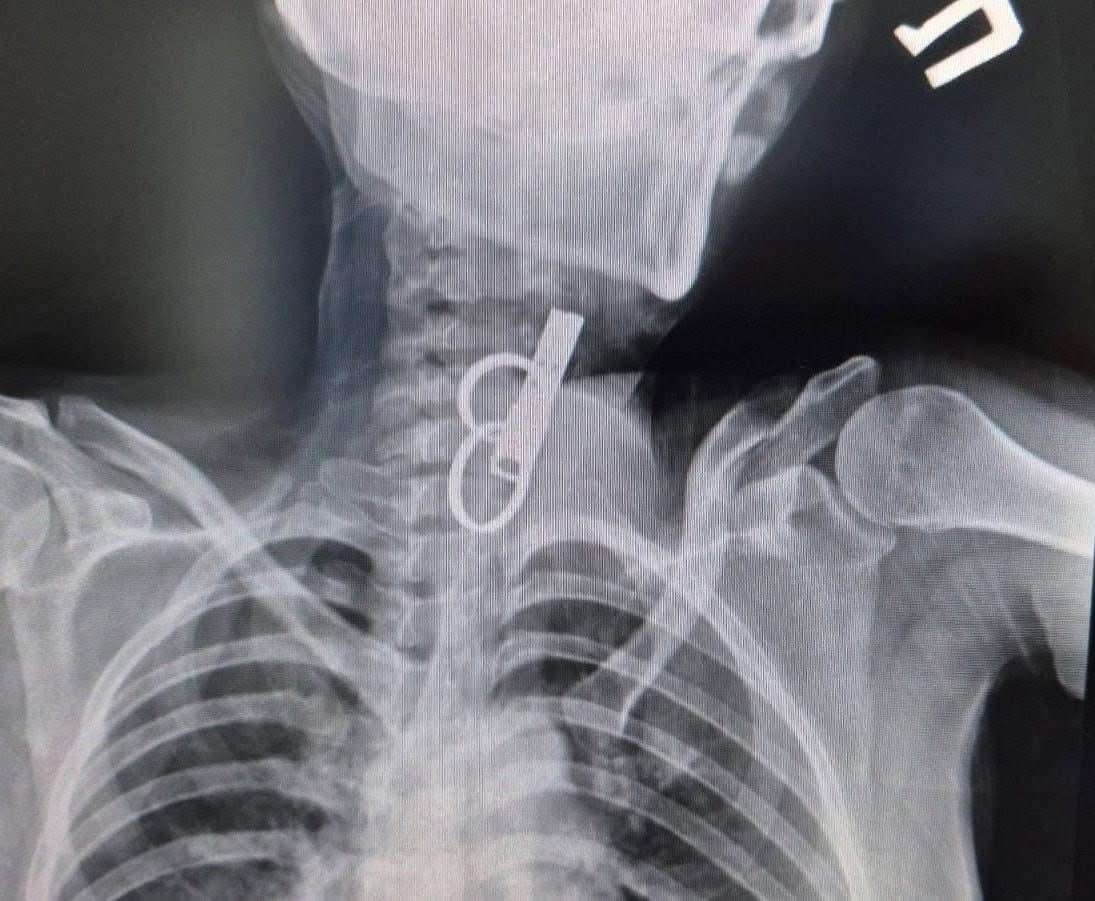

На Тернопільщині лікарі витягли зі стравоходу жінки ключ від дверей

40-річна пацієнтка близько тижня жила з ключем у стравоході — вона проковтнула його, щоб родичі не змогли потрапити до її помешкання.

Жінку доправили до лікарні у важкому стані, тож рішення про операцію ухвалювали терміново.

Після втручання їй встановили гастростому для відновлення стравоходу. Наразі стан пацієнтки стабільний.

За словами хірурга-ендоскопіста Олександра Садового, у більшості подібних випадків хворих не вдається врятувати.

Фото: КНП Гусятинська КЛ